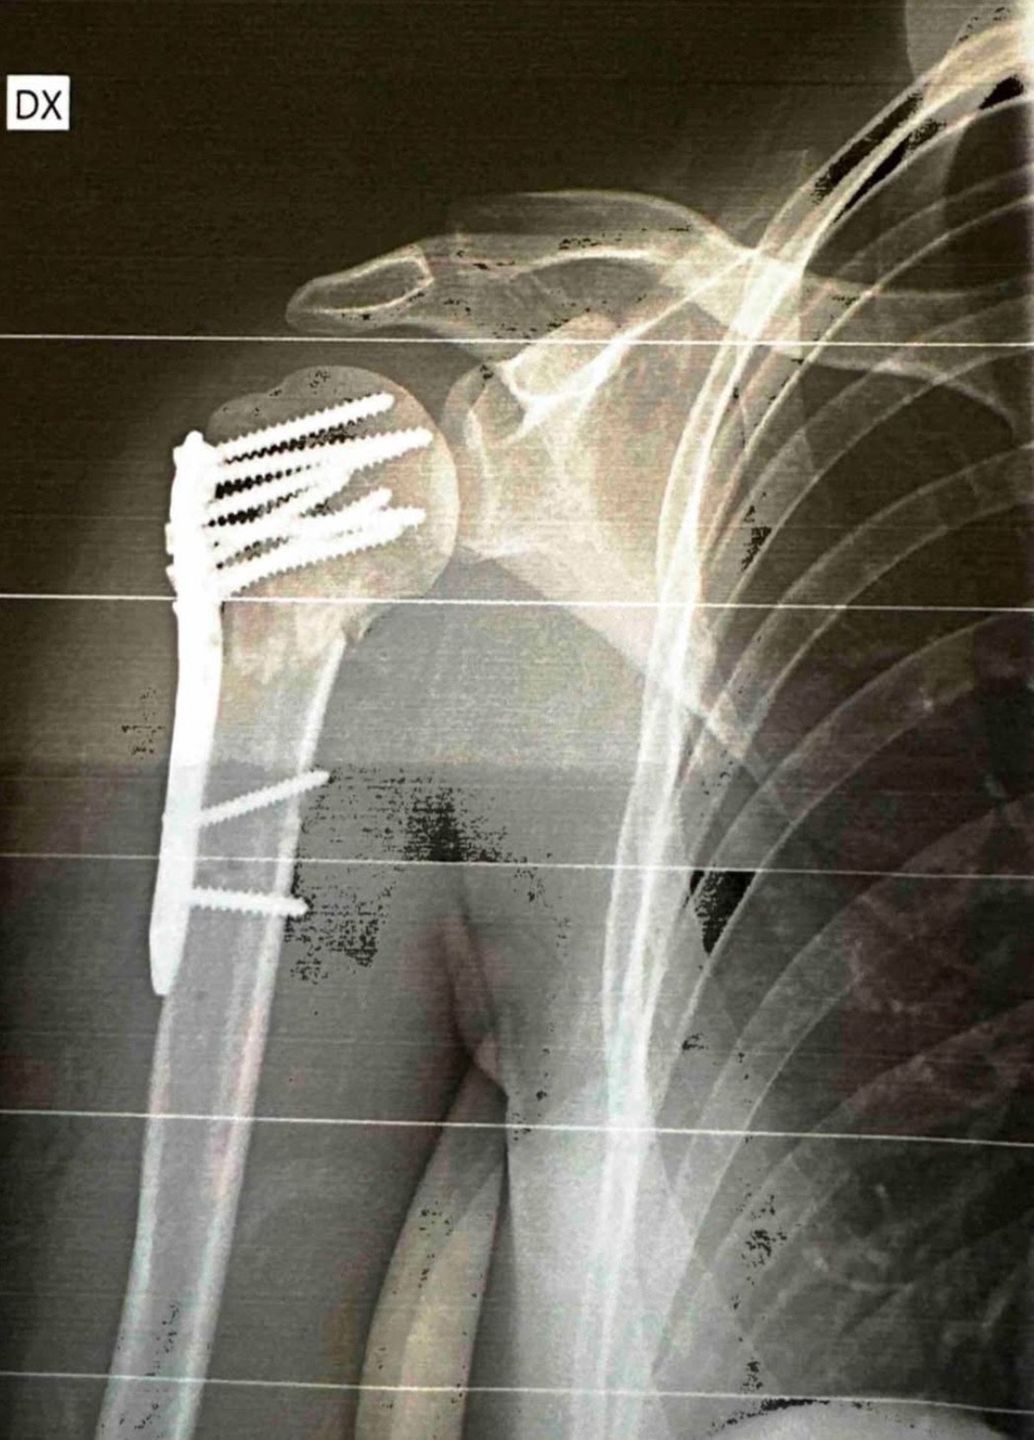

33-latka kilka dni temu wyjechała z bliskimi na narty do Włoch. Zimowe szaleństwo okazało się dla niej tragiczne w skutkach. Rogowska-Lichnerowicz zderzyła się z wpatrzonym w ekran telefonu snowboardzistą. Trafiła do szpitala, gdzie stwierdzono, że uraz ramienia jest poważniejszy, niż początkowo zakładano. Podczas operacji konieczne było użycie 9 śrub.

Teraz, kilka dni po wypadku dziennikarka podzieliła się w mediach społecznościowych zdjęciem, na którym pokazuje, jak wygląda jej rekonwalescencja. Do postu na Instagramie dołączyła też między innymi fragment badania rentgenowskiego i poinformowała, jak się teraz czuje.

Dziś mija 4 doba od operacji i 4 najgorsza w moim życiu pod względem bólu, który w skali 1-10 oceniam na 15. Finalnie zamiast trzech blach mam dziewięć śrub i codziennie faszeruję się lekami przeciwbólowymi, żeby jakoś wytrzymać. Leżenie to jedyna komfortowa pozycja, a każdy krok to milion spalonych kalorii - zaczęła wpis.

Zdjęcie rentgenowskie po operacji dziennikarki

Zdjęcie rentgenowskie po operacji dziennikarki © Instagram